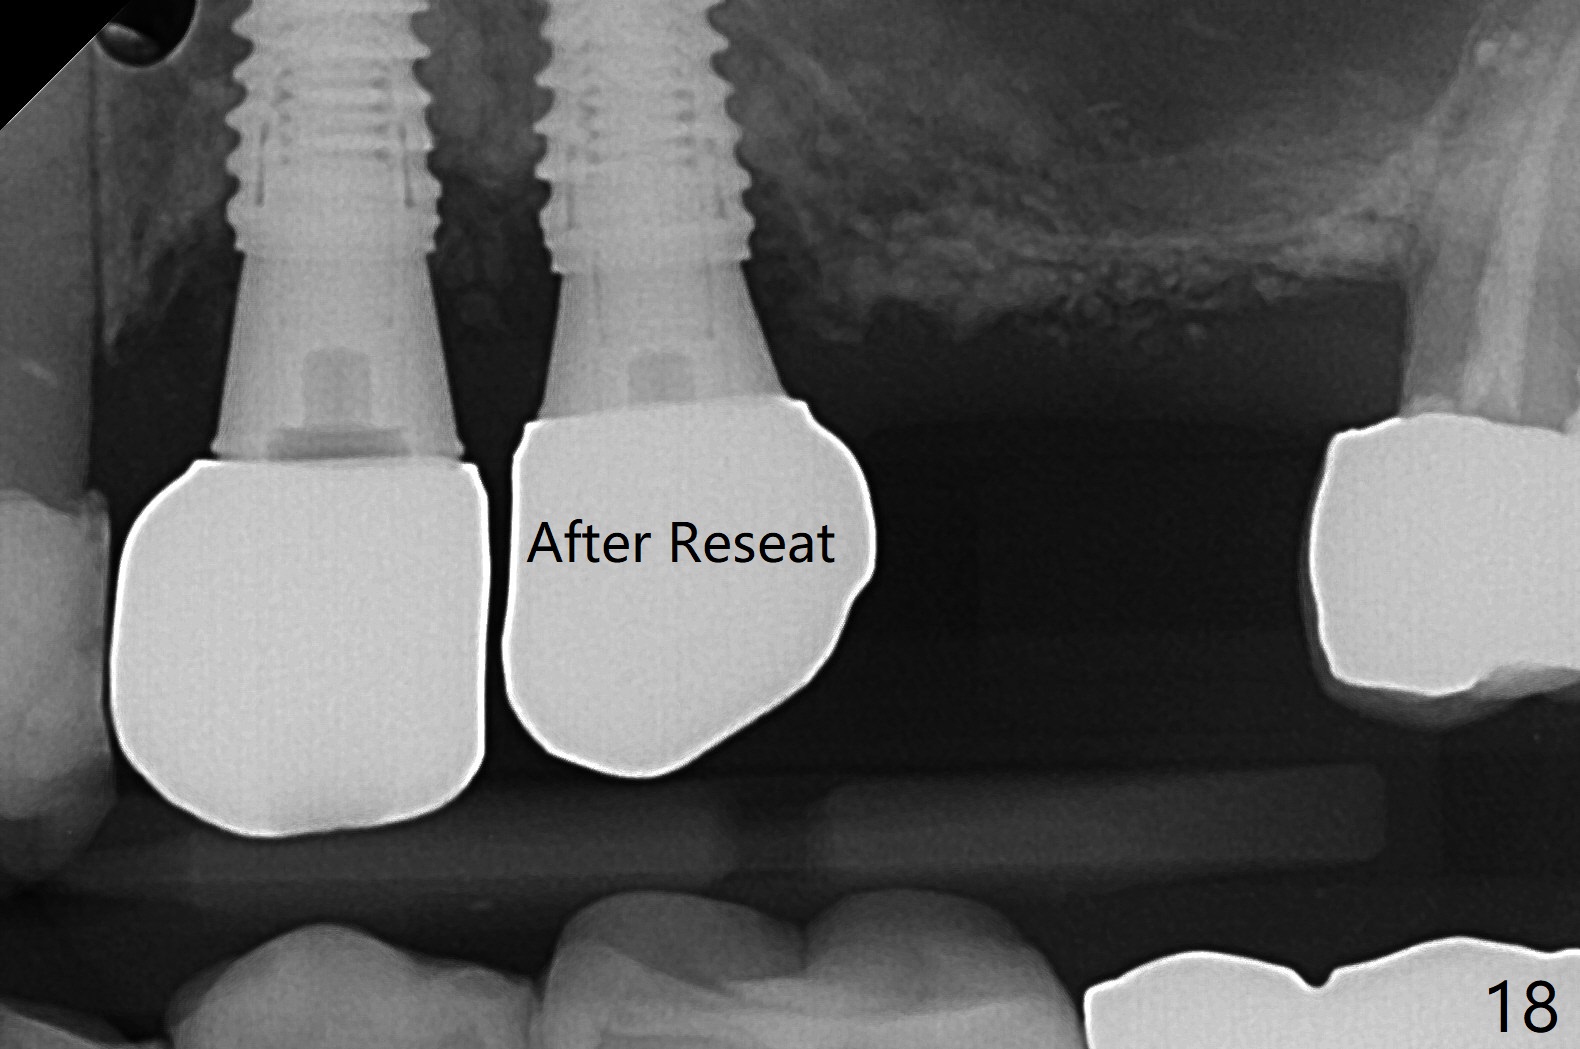

Osteotomy at #3 is performed last (Fig.1,2); as planned, a 4 mm cortical tap is used with guide for sinus lift. Unfortunately the sinus membrane is perforated. Implant placement is aborted. Instead Osteogen plug is inserted into the osteotomy, which is fixed in place by acrylic extending from the provisional at #4. Osteotomy for #3 implant will be attempted with control of the depth in 4 months. The patient has allergy to Amoxicillin (rash). When switching to Clindamycin, she develops diarrhea and loses 10 pounds. There is no abnormality at the site of #3 or 4 nearly 3 months postop (Fig.3). The next surgery will be most likely conducted without antibiotic 4 months postop. Try to draw blood for PRF. Take PA for #12 and 13 for possible impression. Remove the 3 temporary crowns, seat the guide across the arch and use no-stop fixture mounts at #4, and possibly 12 and 13. Follow the original drill sequence (check perforation after each drill, Fig.11) and use DIONavi sinus approach kit. Also load an appropriate stop for the round bur for sinus lift before hand. Mixture allograft with Metronidazole and PRF. In fact everything goes on as smoothly as planned. Osteotomy at #3 is underprep (3.5 mm in diameter drill instead of 4.0). The sinus floor appears to remain to be absent; 3.2 mm round bur is used for lift, alternating with water pumping. Following insertion of 3 pieces of PRF membranes and Vanilla Graft (Fig.4 *), a 4x10 mm dummy implant is placed. After additional bone graft (Fig.5 *), a final 4.5x7.3 mm implant is placed ~10 Ncm. The implant is placed deeper ~ 1 mm, followed by a 5.5x3 mm healing abutment (Fig.6). The implants at #12 and 13 seem to have osteointegrated (Fig.7). Impression is taken for #4, 12 and 13 with limited vertical space (Fig.8,9). An implant at #14 is being considered. There is faint bone graft around the apex of the implant 4 months postop (Fig.10). The implant sustains 25-30 Ncm torque when a 5.2x4(3) mm cemented abutment is placed. A permanent crown is cemented nearly 5 months postop (Fig.11). For the best cosmetic and masticating results, the occlusal surface should have certain degree of morphology, such as the buccal cusps (Fig.12 white curved lines). The abutment at #3 is placed and torqued to 30 Ncm before re-cementation of the repaired crown (increased occlusal surface contact). In fact the abutment at #4 is incompletely seated with a gap (Fig.13 <). The composite at #5 is dislodged while #3 crown is being repaired (*). The abutment at #4 is loose >1 year post cementation. The abutment remains incompletely seated (gap and longer apical space (double arrows)) when the abutment/crown complex rotates lingual mesiobuccal (Fig.14 curved arrow). Further proximal reduction and lingual rotation distobuccal leads to complete seating (Fig.15). It appears that incomplete seating at #13 is associated with hex mismatch (Fig.16, large apical space), which will be fixed next visit. One week later, the crown and abutment of #4 are seated together after crown repair (Fig.17). Since the abutment margin is subgingival, the crown is cemented, removed with abutment for residual cement removal and reseated with the abutment with torque at 30 Ncm. After this, the crown and abutment of #13 is reseated after mesiobuccal surface is trimmed (Fig.18), followed by pick up impression. A few days later, the crown/abutment are inserted together smoothly, the former cemented and the complex unscrewed for residual cement removal and last torqued at 30 Ncm without any X-ray confirmation.